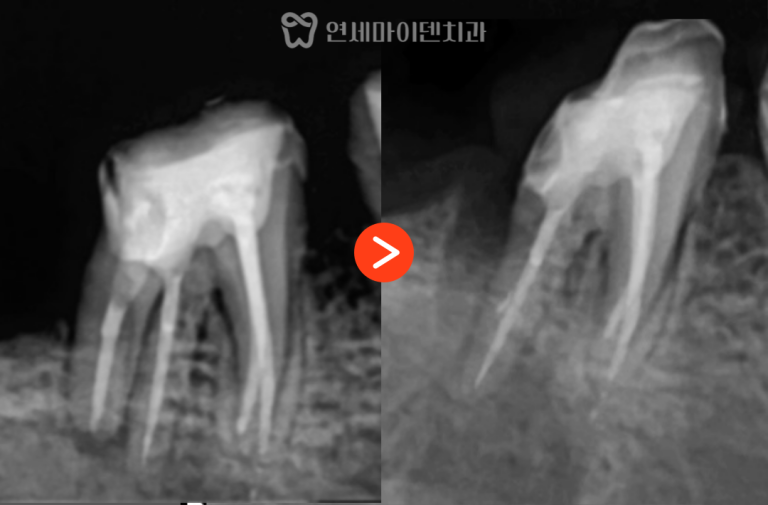

치근절제술 증례: 5년 경과 저희 병원에는 신경치료 후에도 통증이 지속되거나,경과가 좋지 않아 대학병원으로 의뢰되기 전마지막으로 내원하시는…

안녕하세요, 소중한 치아를 지키는연세마이덴치과 닥터꼬집입니다. 많은 분들이 신경치료 후 염증이 재발했을 때,재신경치료를 시도할지, 임플란트로 바로 가는게…